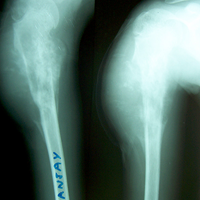

Case:7 GCT Humerus

Spine Surgeon Best In Rajasthan

Pre-Op

Sports Injuries Doctor

3 Years follow-up

Orthopedic Oncology Doctor In Ahmedabad

5 Years follow-up